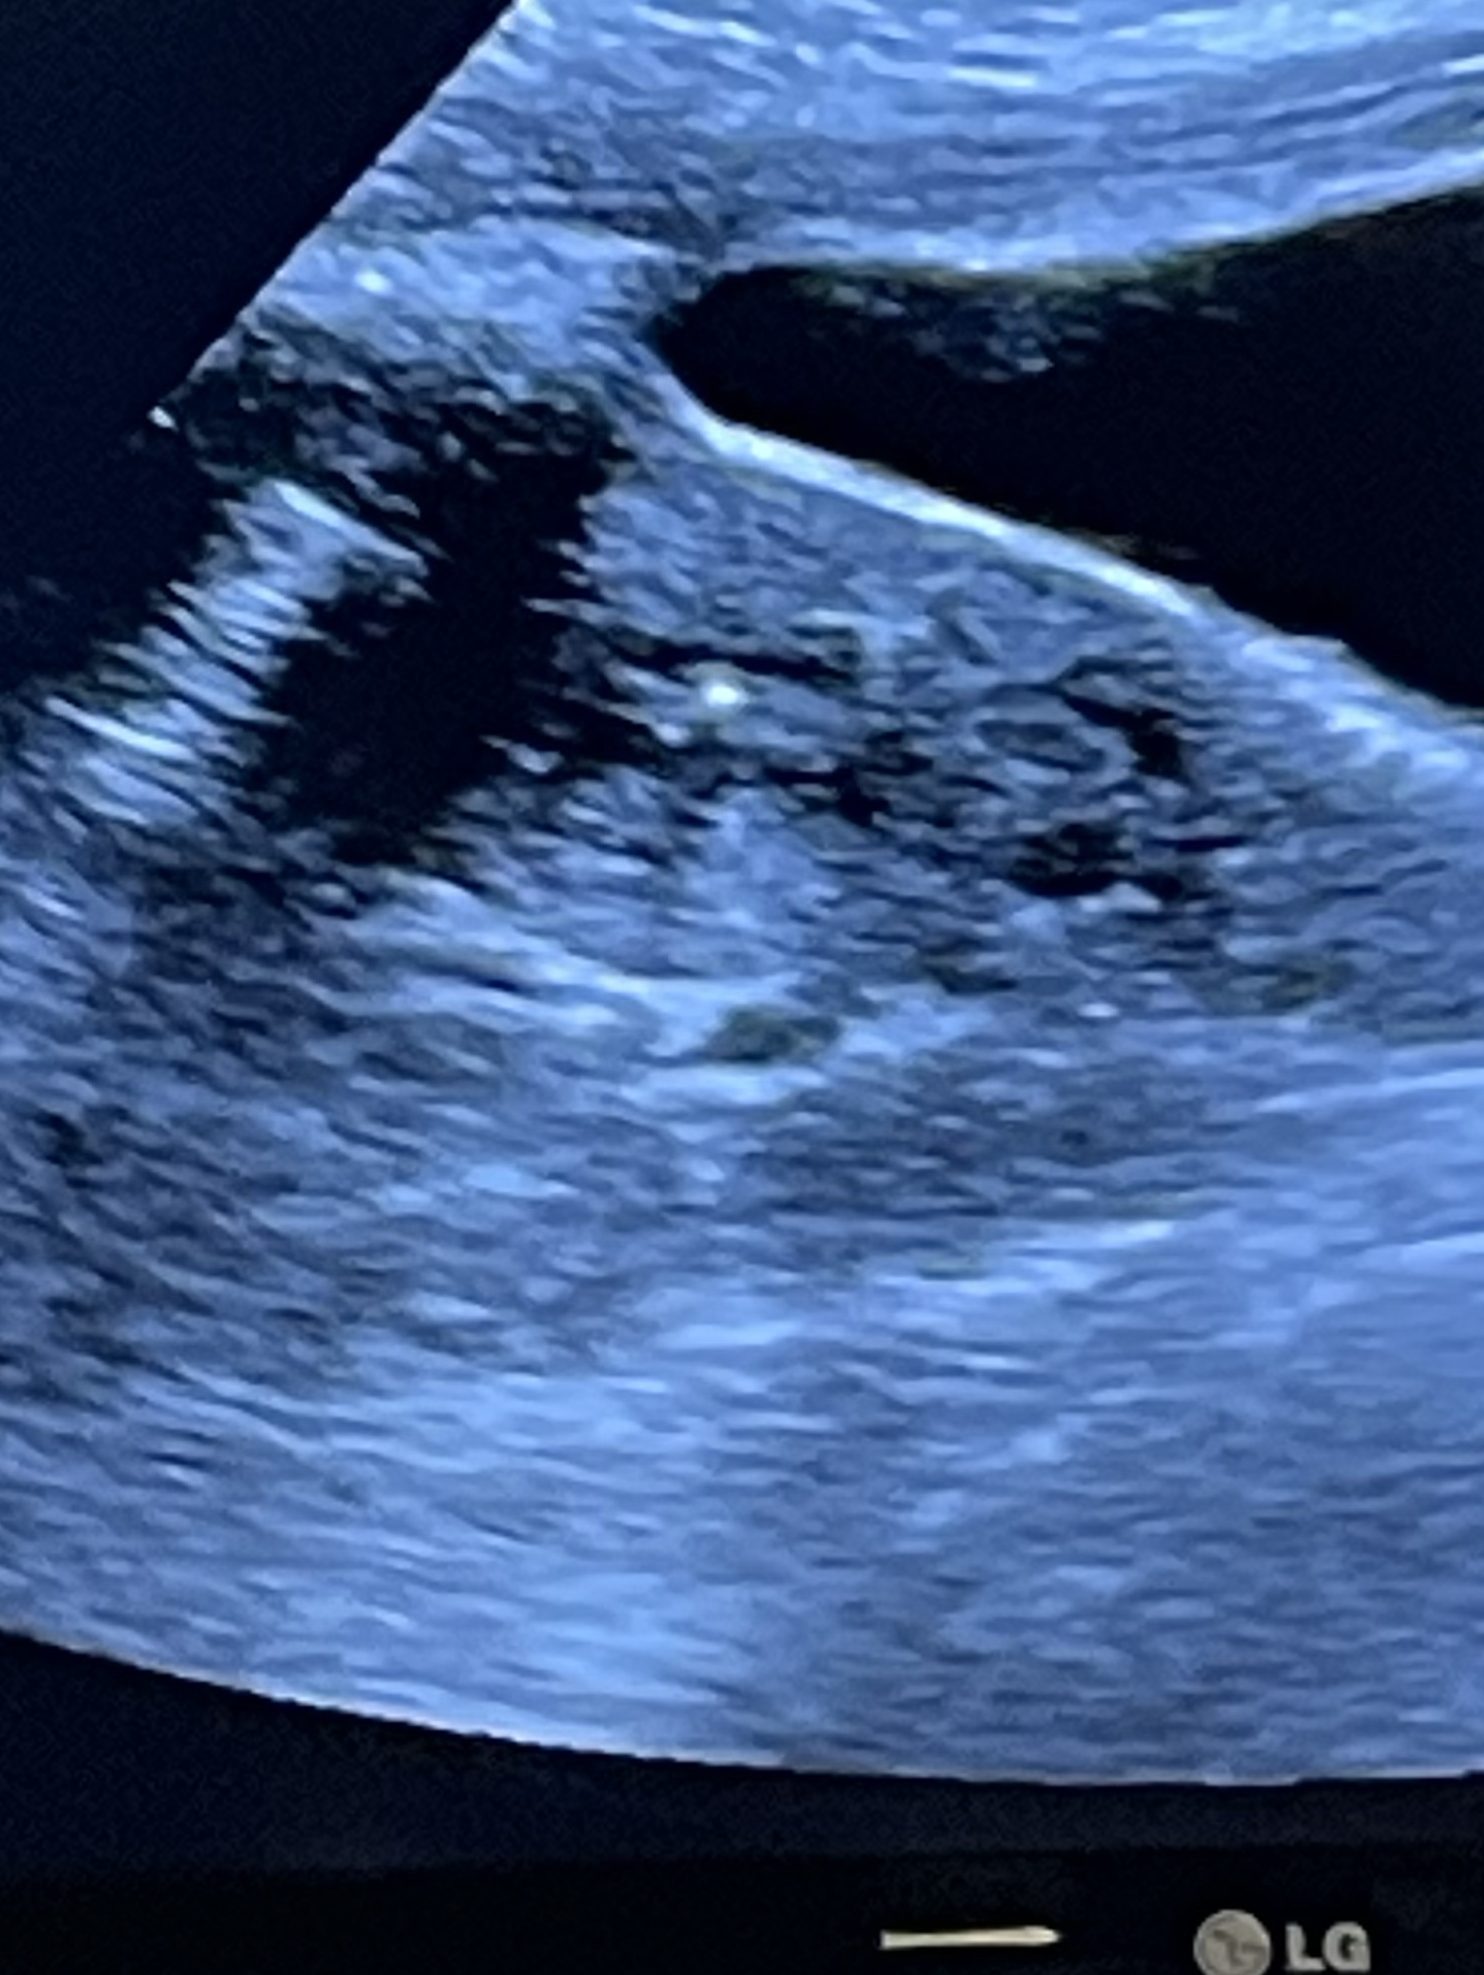

Quickly after checking in we are changed into our hospital gowns and I have my transfer day socks from my dear friend, Lindsey. I honestly can’t even remember the conversations that we had while waiting. Hehe. When the doctor comes in, she shows us our baby’s first picture. It’s on a microscope of course, but it’s a beautiful 5-day thawed embryo. For the actual transfer they guide the embryo right into the uterus while monitoring on an ultrasound. And just like that it is done! That tiny bright light you see on the ultrasound image below is our little nugget.